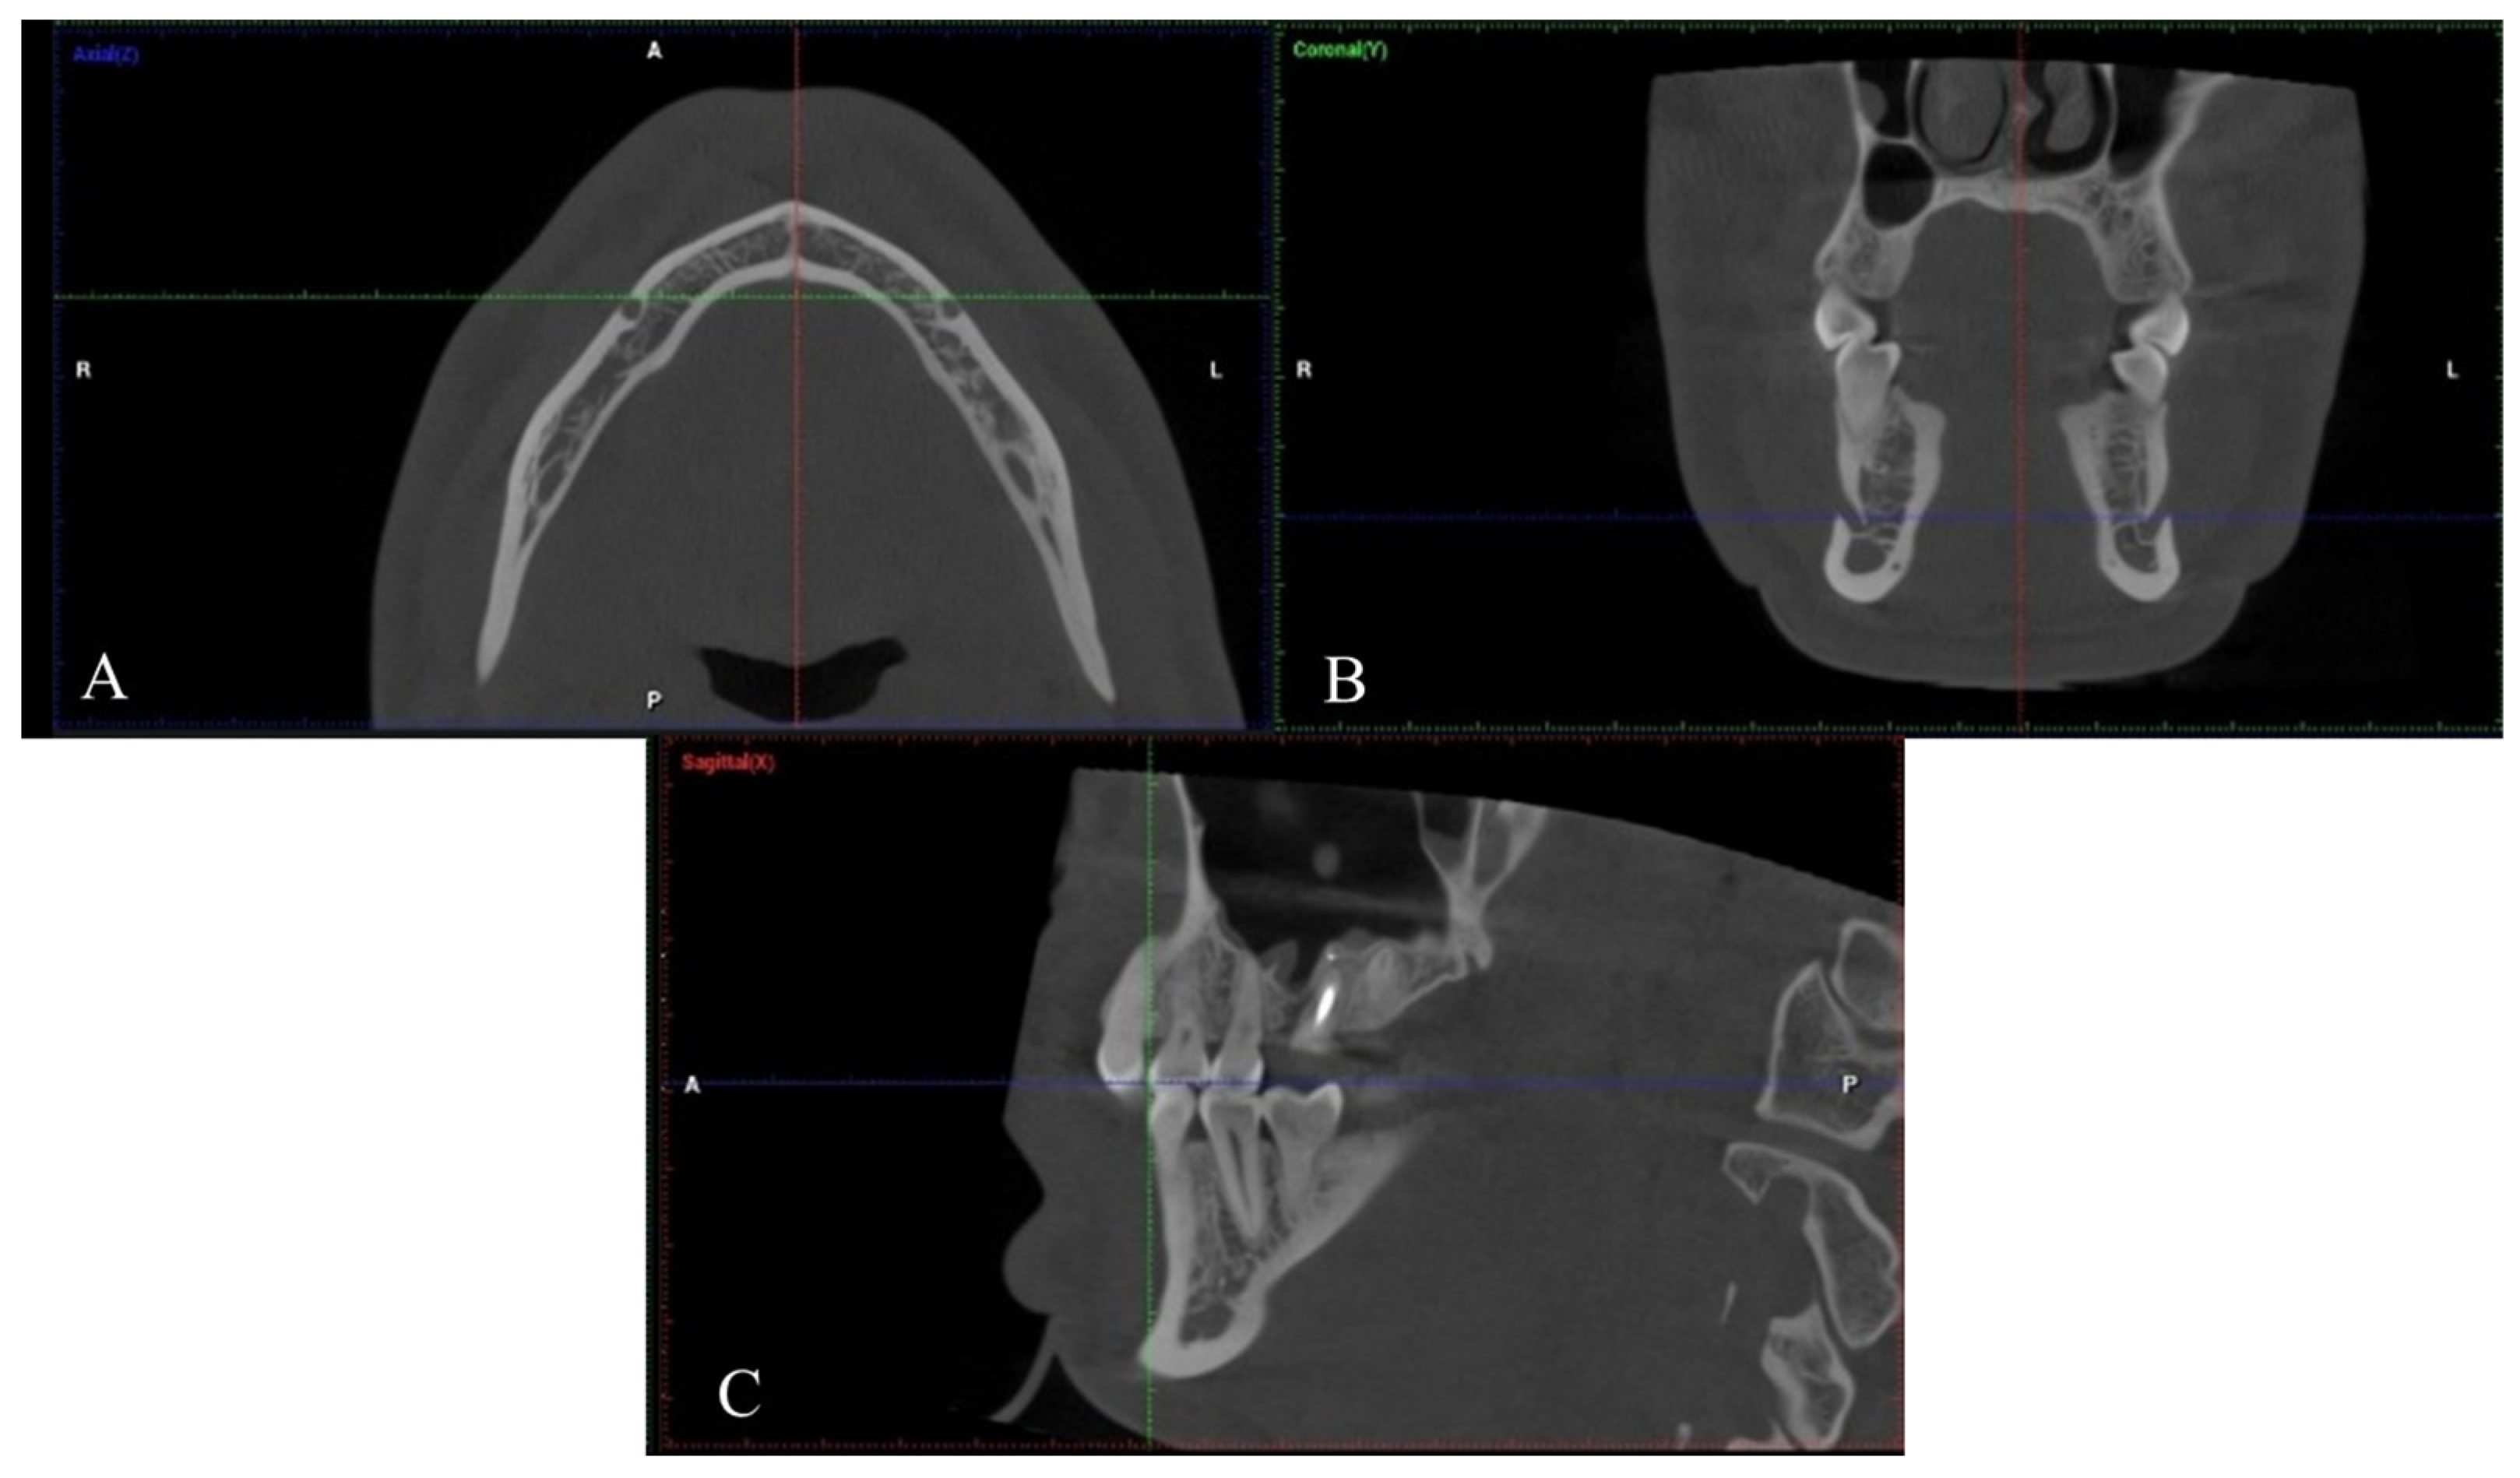

2. Materials and Methods